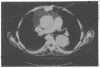

An infected graft in the ascending aorta was managed by use of an omental pedicel graft and local irrigation with a dilute suspension of aqueous providone iodine. This conservative approach is an alternative to the high risk procedure of graft replacement. The large abscess cavity associated with the aortic prosthesis was diagnosed by computed tomography.